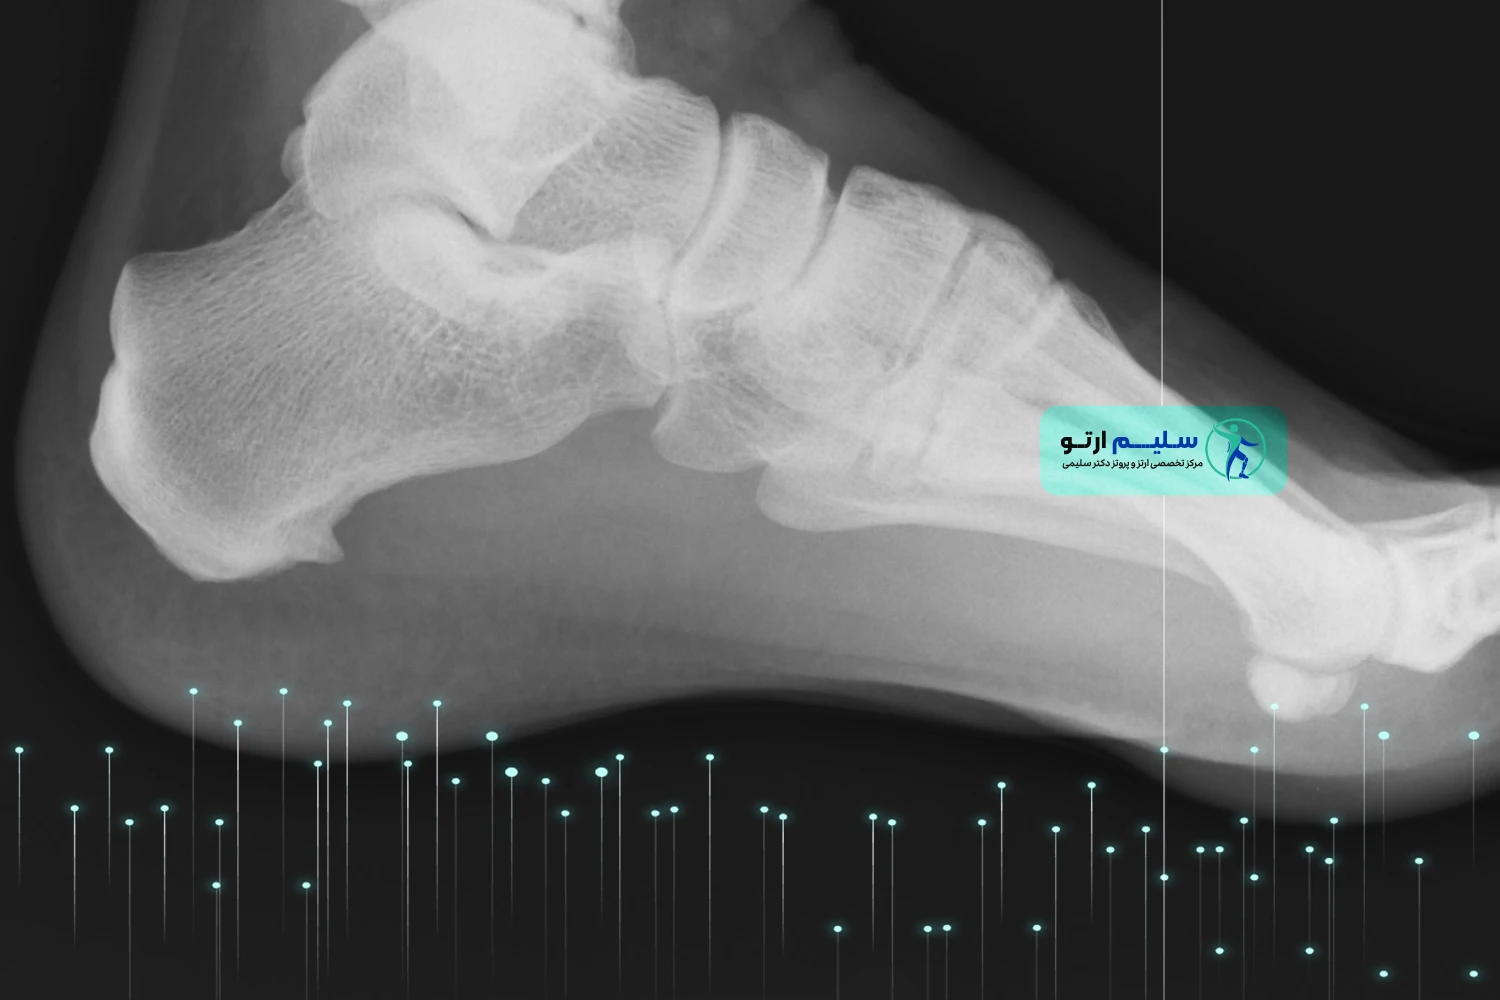

خار پاشنه،که در زبان انگلیسی با نام های “Heel Spur” یا “Calcaneal Spur” شناخته می شود، در واقع رسوبی از کلسیم است که در زیر استخوان پاشنه پا (کالکانئوس) تشکیل می شود. این زائده استخوانی کوچک، می تواند به سمت جلو، به سمت قوس پا،یا در موارد نادرتر، به سمت عقب پاشنه رشد کند.

به بیان ساده، خار پاشنه یک برآمدگی استخوانی کوچک و نوک تیز یا قلاب مانند است که در اثر تجمع تدریجی کلسیم در محل اتصال رباط های کف پا به استخوان پاشنه ایجاد می شود . این زائده نتیجه ی پاسخ طبیعی بدن به فشار و کشش مکرر و طولانی مدت بر روی این ناحیه است . بدن در تلاش برای ترمیم و تقویت بافت های آسیب دیده، شروع به رسوب کلسیم می کند که به مرور زمان منجر به تشکیل این ساختار استخوانی می شود . این عارضه غالباً با پلانتار فاشیئیت (التهاب فاشیای کف پا) همراه است، به طوری که حدود نیمی از بیماران مبتلا به پلانتار فاشیئیت، خار پاشنه نیز دارند.

خیر، وجود خار پاشنه در عکس رادیوگرافی لزوماً به معنای وجود درد نیست . بسیاری از افراد خار پاشنه دارند اما هیچ دردی احساس نمی کنند. درد زمانی ایجاد می شود که این زائده با بافت های نرم اطراف، به خصوص فاشیای پلانتار، برخورد کرده و باعث التهاب و آسیب شود.